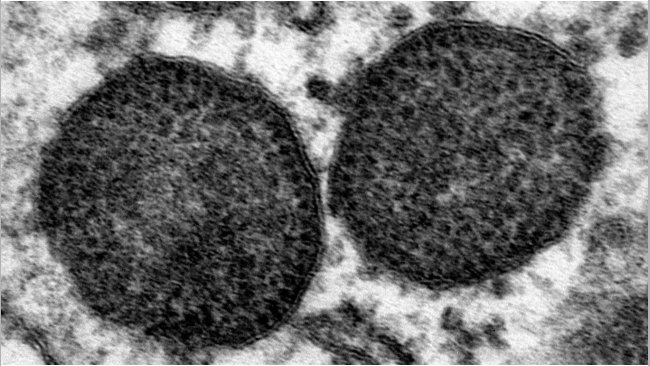

La disminución de los genotipos PCV2a y PCV2b en el tiempo y el aumento de PCV2d en 2012 puede deberse más a otros factores desconocidos que a la selección inmunológica resultante de la vacunación en base a PCV2a.

La vacunación frente a PCV2 es casi universal, ¿ha disminuido la presencia del virus tras 6 años de vacunación? ¿Podrían cambiarse las políticas vacunales?

Todas las vacunas disponibles en el mercado europeo y norteamericano están basados en el genotipo PCV2a, mientras que los que tienen más prevalencia son los PCV2b y PCV2d. Pese a que se ha demostrado un nivel significativo de protección cruzada entre estos tres genotipos, sería interesante evaluar si la eficiencia vacunal sería equivalente frente a todos estos genotipos.